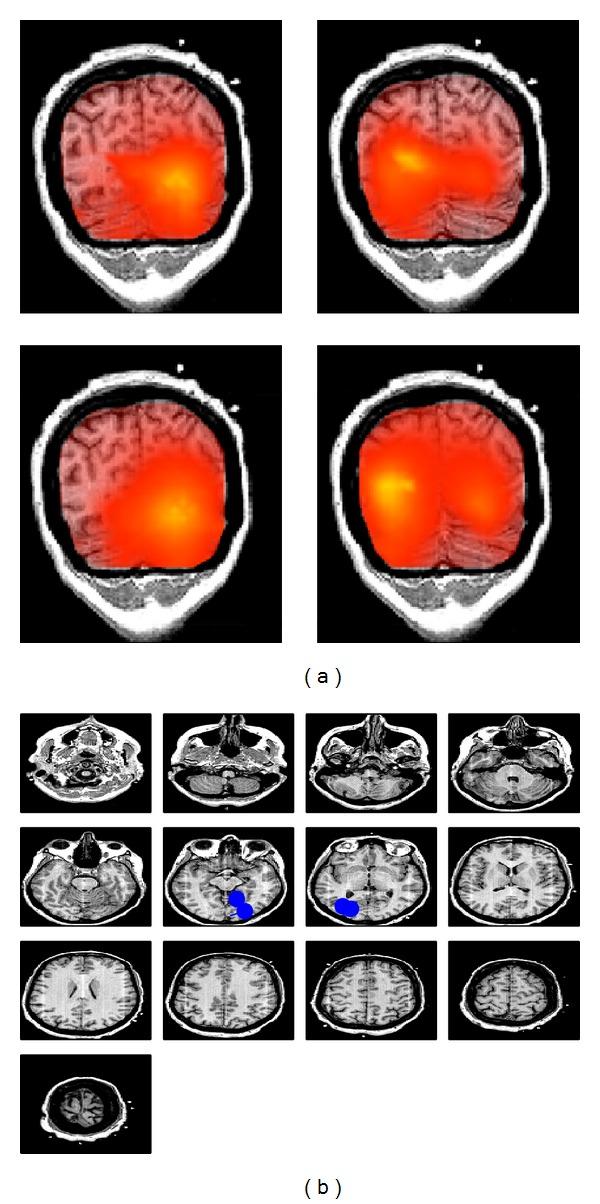

To address the problem of mixing in EEG or MEG connectivity analysis we exploit that noninteracting brain sources do not contribute systematically to the imaginary part of the cross-spectrum. Firstly, we propose to apply the existing subspace method "RAP-MUSIC" to the subspace found from the dominant singular vectors of the imaginary part of the cross-spectrum rather than to the conventionally used covariance matrix. Secondly, to estimate the specific sources interacting with each other, we use a modified LCMV-beamformer approach in which the source direction for each voxel was determined by maximizing the imaginary coherence with respect to a given reference. These two methods are applicable in this form only if the number of interacting sources is even, because odd-dimensional subspaces collapse to even-dimensional ones. Simulations show that (a) RAP-MUSIC based on the imaginary part of the cross-spectrum accurately finds the correct source locations, that (b) conventional RAP-MUSIC fails to do so since it is highly influenced by noninteracting sources, and that (c) the second method correctly identifies those sources which are interacting with the reference. The methods are also applied to real data for a motor paradigm, resulting in the localization of four interacting sources presumably in sensory-motor areas.

为了解决 EEG 或 MEG 连接分析中的混叠问题,我们利用非交互脑源不会系统地对互谱的虚部做出贡献这一特性。首先,我们建议将现有的子空间方法“RAP-MUSIC”应用于从互谱虚部的主导奇异向量中找到的子空间,而不是应用于传统上使用的协方差矩阵。其次,为了估计与每个相互作用的源,我们使用了一种改进的 LCMV-波束形成方法,其中每个体素的源方向是通过相对于给定参考最大化虚相干性来确定的。只有在相互作用的源数量为偶数的情况下,这两种方法才能以这种形式应用,因为奇数维子空间会塌缩到偶数维子空间。模拟表明:(a)基于互谱虚部的 RAP-MUSIC 准确地找到了正确的源位置;(b)传统的 RAP-MUSIC 无法做到这一点,因为它受到非相互作用源的高度影响;(c)第二种方法正确地识别了与参考相互作用的那些源。这些方法也应用于运动范式的真实数据,导致四个相互作用的源在感觉运动区域的定位。